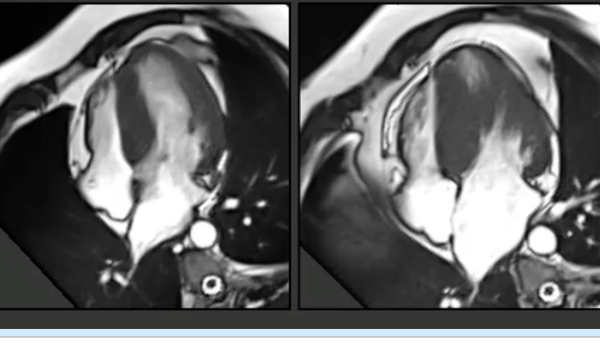

A common clinical presentation of LBBB induced cardiomyopathy is described in this post. It is always dilemma that if LBBB is cause or effect of dilated cardiomyopathy. However CMR can help in differentiating it from other causes and also in predicting response to device therapy. Utilise CMR to the fullest.